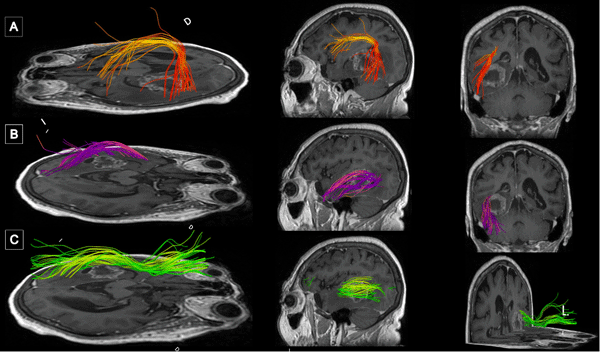

La resonancia magnética (RM) de encéfalo con gadolinio evidenció una lesión expansiva heterogénea, con áreas centrales de aspecto quístico y degeneración necrótica, localizada en la topografía temporomesial izquierda de aproximadamente 28 × 27 mm en plano axial y 29 × 26 mm en plano coronal, con realce heterogéneo tras la administración de contraste endovenoso. En secuencia de susceptibilidad magnética presentaba signos de restos de hemosiderina y/o microcalcificaciones. En el asta occipital y el atrio ipsilateral del ventrículo lateral, se evidenciaron formaciones quísticas con refuerzo periférico. La lesión descripta presentaba edema perilesional que comprometía el lóbulo temporal izquierdo y la región parietoccipital ipsilateral. Además, se observó dilatación del tercer ventrículo y ventrículo lateral homolateral. Las cisternas perimesencefálicas se encontraban libres, y las estructuras de la línea media, centradas. Las imágenes obtenidas eran sugestivas de una lesión de origen glial de alto grado (Figura 1). Se complementó con tractografía en la que se observó una disminución de la fracción de anisotropía a nivel del septum sagital con disrupción de las fibras de los tractos arcuato, frontooccipital inferior y longitudinal inferior izquierdo (Figura 2).

Figura 2. Tractografía con reconstrucción 3D de los fascículos asociados. Disminución de la fracción de anisotropía a nivel del septum sagital con disrupción de las fibras de los tractos A) Arcuato izquierdo. B) Frontooccipital inferior izquierdo. C) Longitudinal inferior izquierdo.